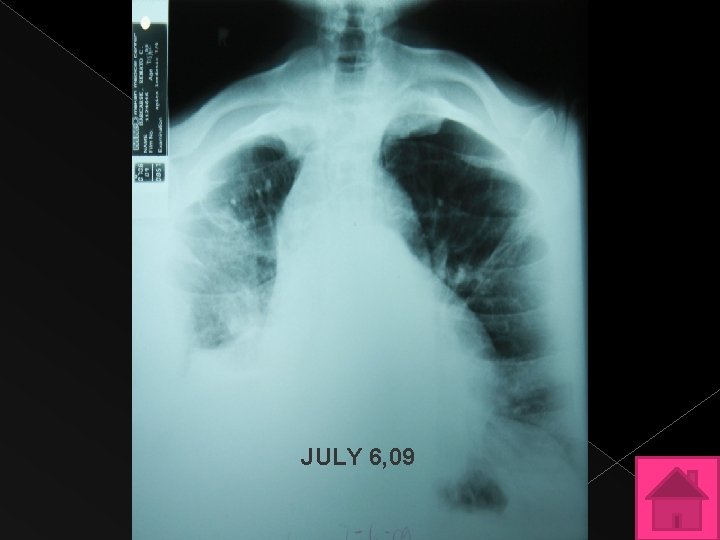

LABORATORIES AND ANCILARIES Chest x-ray July 6, 2009 Decreased in the pleural density at the right mid-lower outer lung with blunting of the costophrenic sulcus. No layering seen in the right lateral decubitus view. Loculated pleural effusion and /or thickening considered. Underlying parenchymal pathology not ruled out. The heart is not enlarged.

JULY 6, 09